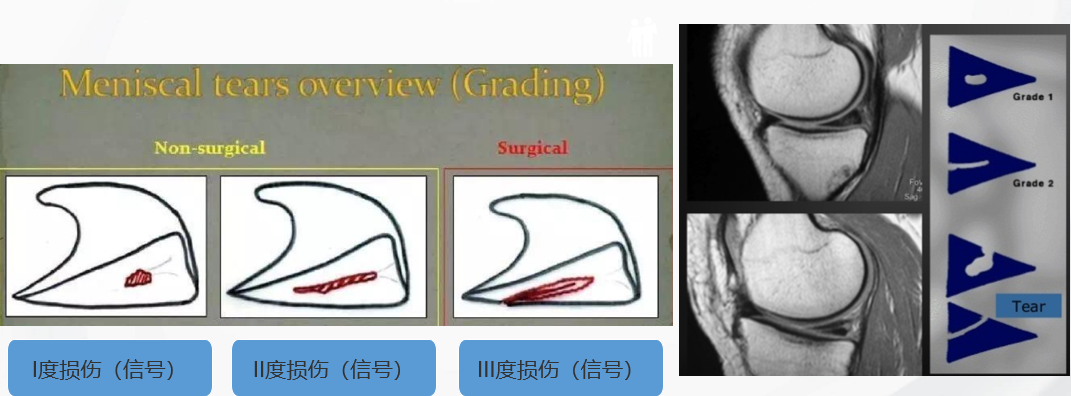

半月板损伤的三类信号